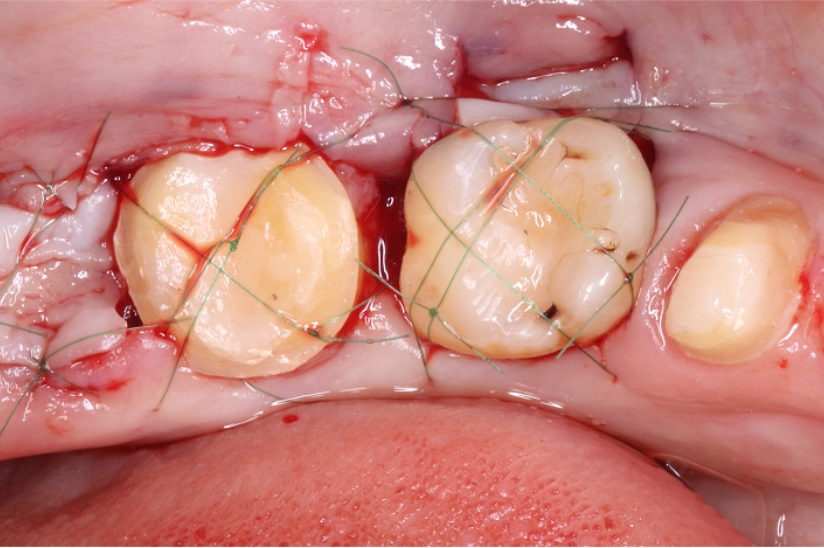

自家歯牙移植と根管治療で

天然歯を保存した症例

Before

Under Treatment

主訴

歯を残せないと言われた。インプラントは先延ばしにしたい

治療内容

自家歯牙移植 / イニシャルトリートメント(大臼歯)レジンコア

治療期間

2ヶ月

治療費用

308,000

治療の

リスク

術後しばらくしてから骨性癒着、外部吸収を起こす可能性があります。